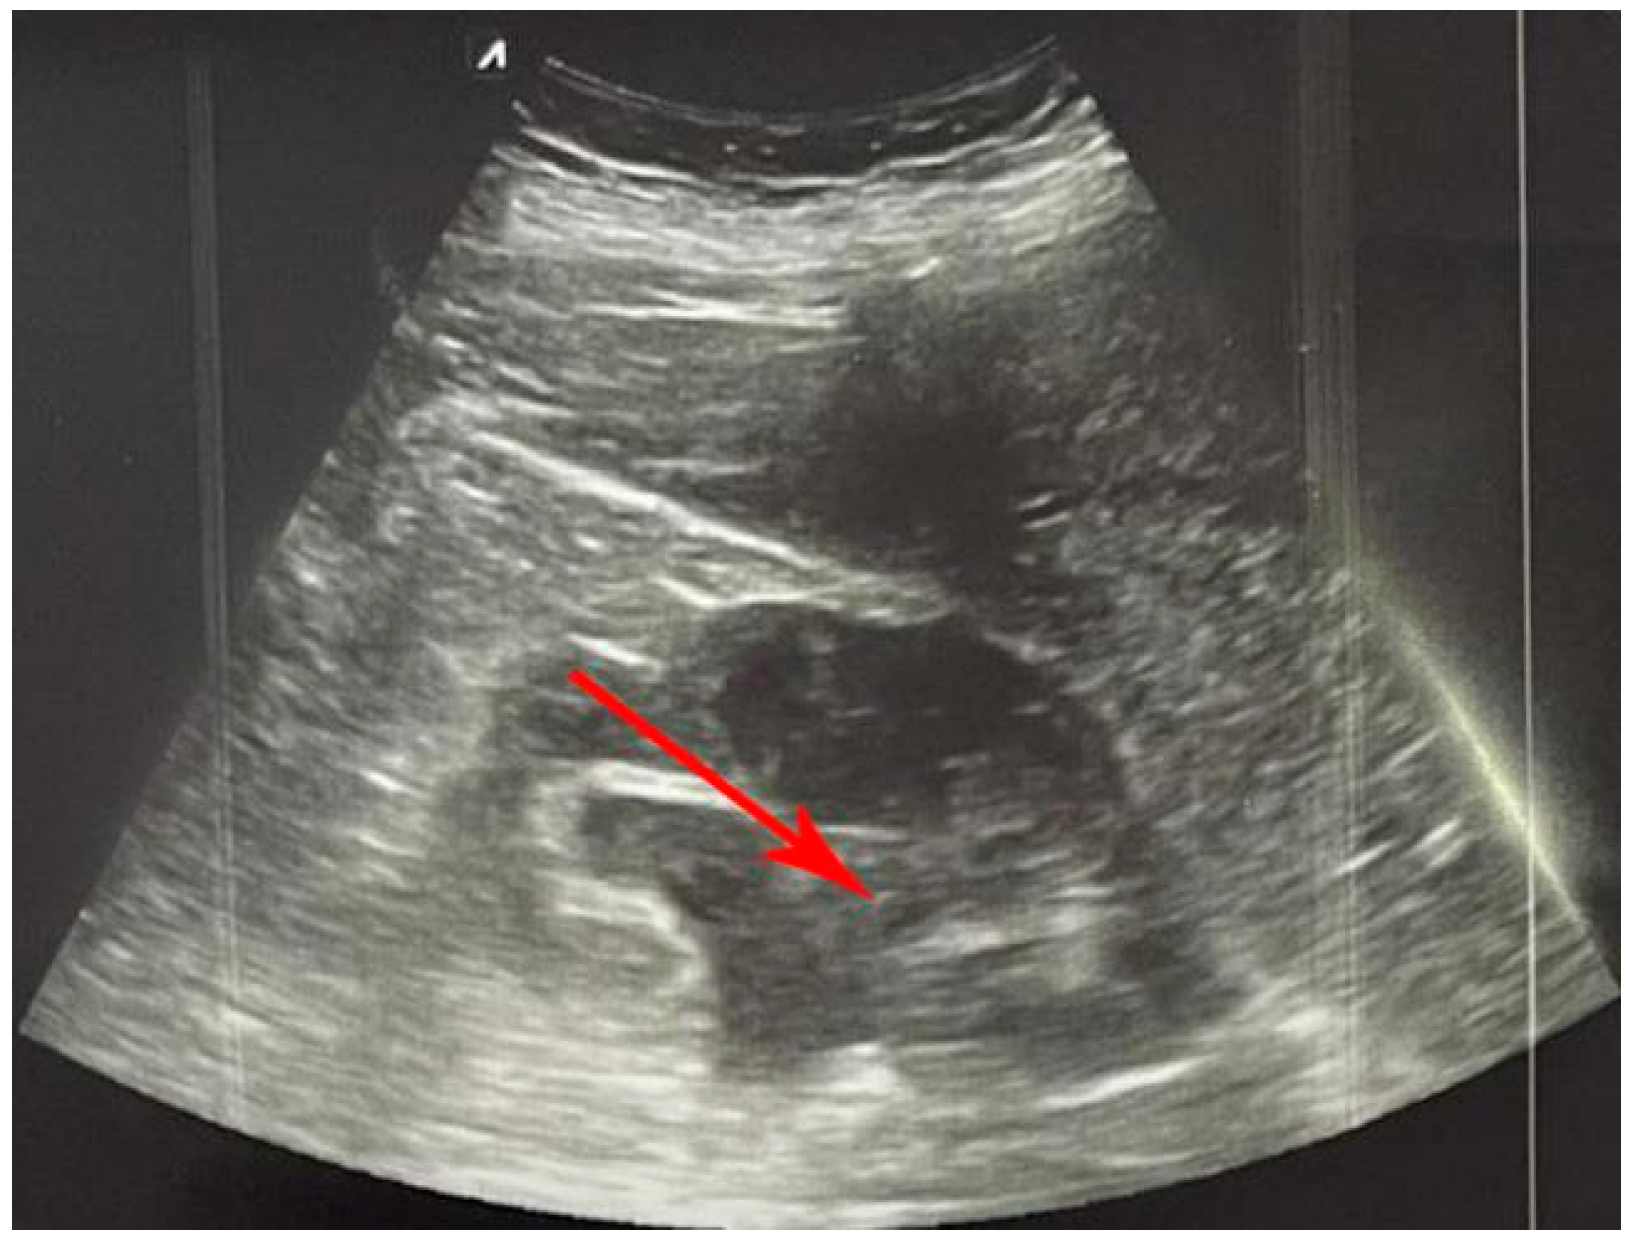

6. Abdominal Aortic Aneurysm